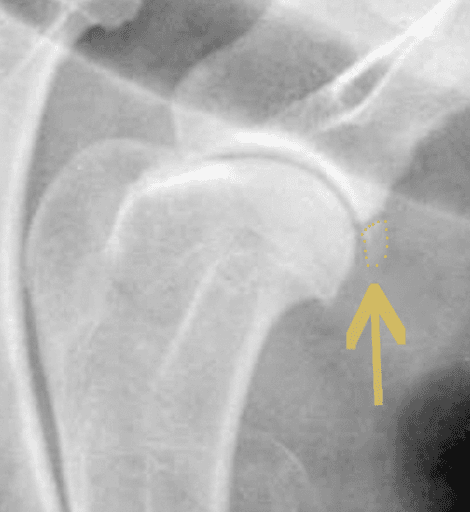

OCD of Caudal Glenoid

Diagnosis:

The disease is suspected when pain is elicited on flexion of the shoulder with physical examination. An x-ray of the shoulder is usually enough to confirm the diagnosis. In some cases, a CT scan may be recommended to identify small lesions not clearly visible on x-rays.